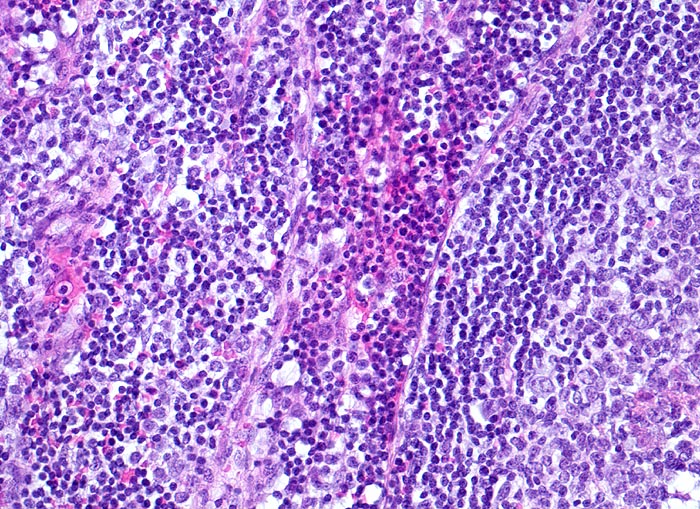

reaktive lymphatische Hyperplasie bei Katzenkratzkrankheit

Das Lymphknotenparenchym ausserhalb der retikulozytär abszedierten Läsionen zeigt eine reaktive Hyperplasie mit Ausbildung von Sekundärfollikeln (Anschnitt eines Keimzentrums). Links davon die interfollikuläre Zone mit einem Sinus, welcher mit Entzündungszellen gefüllt ist (Bildmitte).

Druckschmerzhafte Lymphknotenvergrösserung in der rechten Axilla 2 Wochen nachdem der Patient von seiner Katze an der rechten Hand gekratzt wurde.